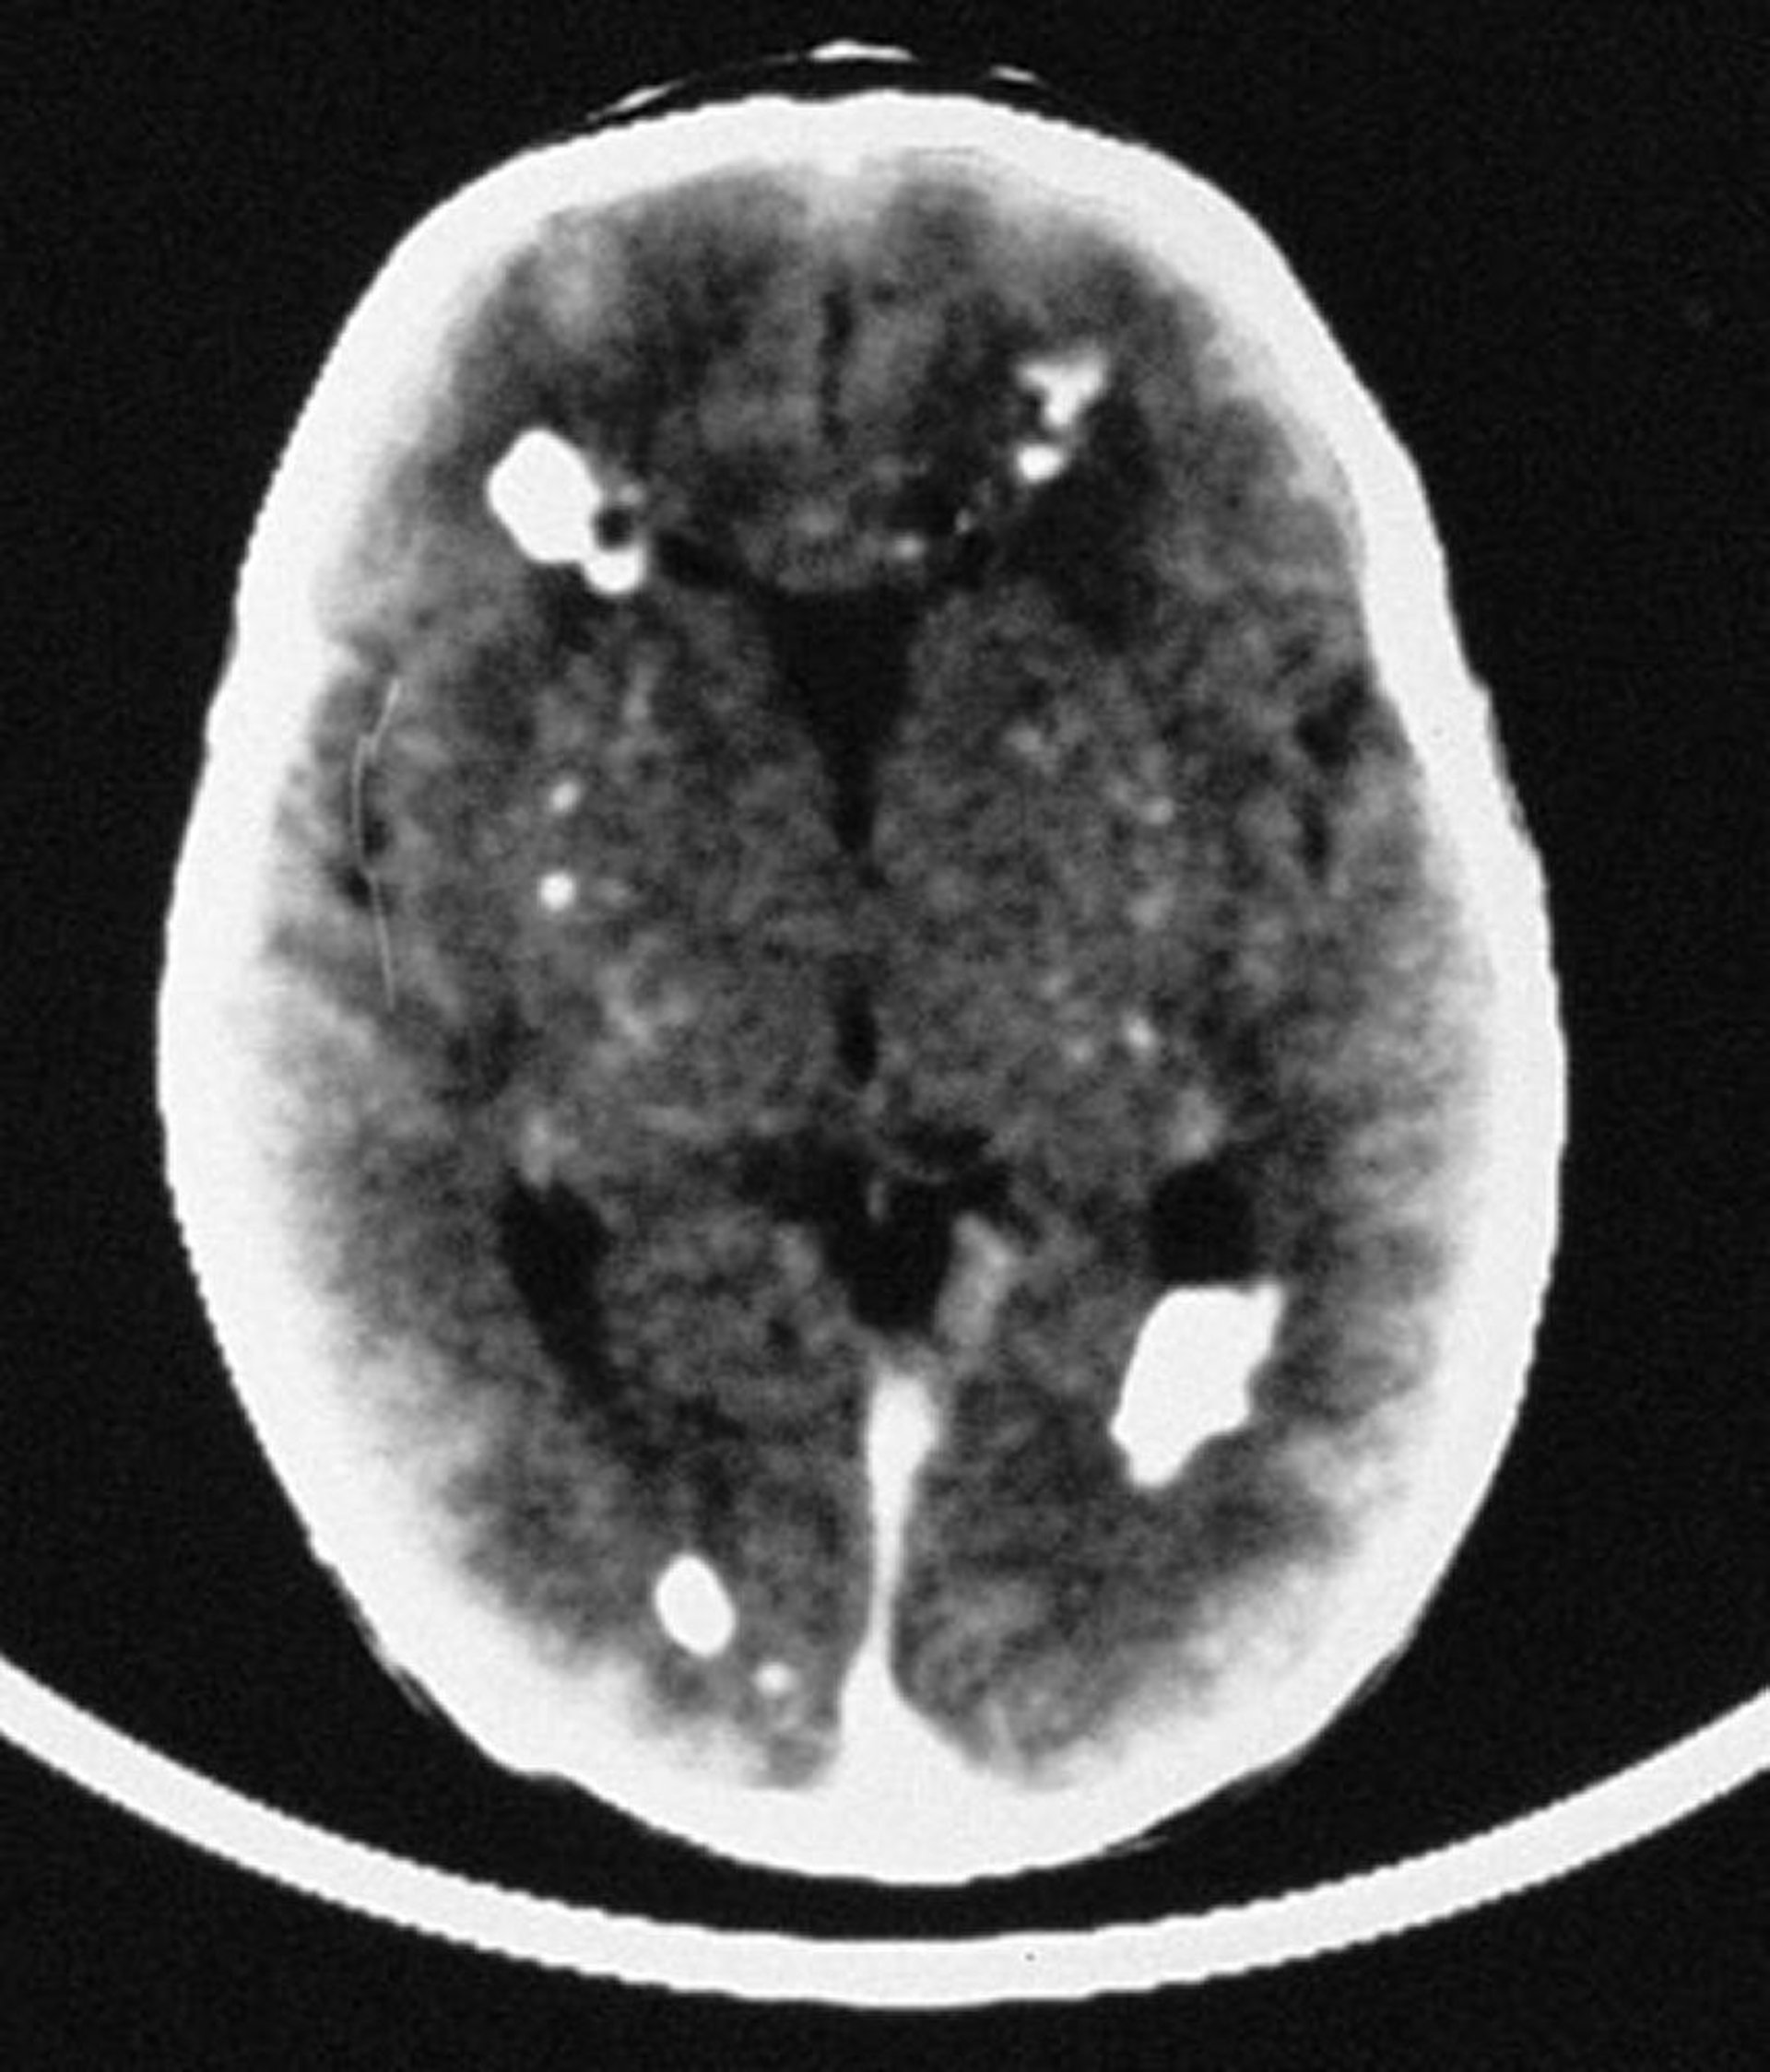

Infezione congenita da cytomegalovirus

In questa immagine, la TC rivela molteplici calcificazioni endocraniche, per lo più di distribuzione periventricolare, ma che coinvolgono anche le strutture vascolari del cervello.